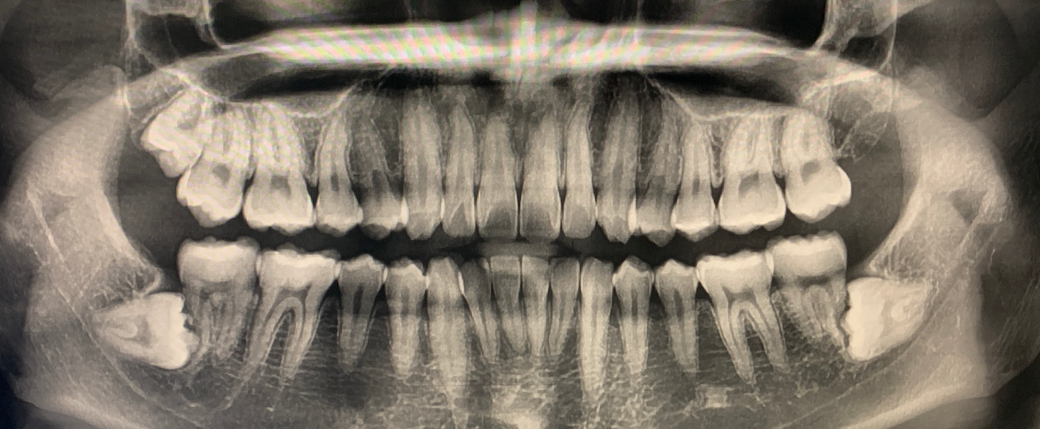

작은 치근단방사선 사진이 있다면 판단에 더 도움이 되겠으나 일단 위의 파노라마 사진으로 보아 수평매복된 사랑니로 인해 그 옆의 두번째 어금니(7번)의 뿌리가 녹아 있는 상태입니다. (치근흡수의 상태) 또한 양쪽 두번째 큰 어금니의 인접면 충치도 의심됩니다.

사랑니 발치 상담해주신 치과의사 선생님께서는 두번째 어금니에 대한 다양한 임상 테스트를 진행한 뒤 살리기 쉽지 않겠다고 판단하여 뽑자고 설명을 해주셨을 것입니다. 또한 두번째 어금니에 손상을 전혀 주지 않고 사랑니를 뽑는 것도 현재 사랑니가 난 방향을 감안하면

쉽지 않습니다. 또한 현재 사랑니가 아래턱에 있는 신경과 매우 근접해 있기 때문에 발치 전 치과CT를 촬영해야 할 수도 있습니다. 사랑니가 완전 매복 상태이므로 CT촬영은 보험이 적용됩니다.

만약 두번째 어금니가 아래만 없는 채로 살게 되는 것이 좀 찝찝하고 불안하다면 hemisection이나 bicuspidization 등으로 최대한 두번째 어금니를 유지해볼 수는 있으나 이는 치과병원급에서 주로 하는 난이도 있는 술식입니다. 해당 용어를 구글에 검색해보시면 다양한 사진이 나오는데 쉽게 말해 뿌리가 2개인 어금니에 한해 할 수 있는 치료 방법이고 한쪽 뿌리만 살리는 것입니다. 현재 치근 흡수가 사랑니와 가까운 한쪽 뿌리에만 진행되었기 때문에 이런 치료를 생각해볼 수는 있겠습니다.

참고로 아래 두번째 어금니가 없으면 맞물리는 위의 두번째 어금니가 점차 그 공간을 향해 내려오게 됩니다. 이를 정출이라고 하며 나중에 아래 두번째 어금니 자리에 임플란트를 심고자 했을 때 공간확보를 위한 추가 처치가 필요할 수도 있습니다.